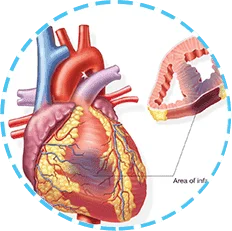

Al no recibir la suficiente sangre y oxígeno, el órgano deja de funcionar y como resultado se produce un infarto o un derrame cerebral.

La hipertensión no solo es la elevación de la presión que puede bajarse tomando una capsula. Es un estado en el cual los vasos sanguíneos se estiran y se adelgazan y en sus paredes aparecen sedimentos de colesterol. Como resultado, esto conduce a una interrupción del flujo sanguíneo y al mal funcionamiento de uno u otro órgano.

Para no permitir la interrupción repentina del funcionamiento de los órganos vitales, es necesario controlar el nivel de colesterol y la presión arterial. Es mejor hacer esto con la ayuda de remedios naturales. En nuestra clínica recomendamos Flebored a los pacientes.